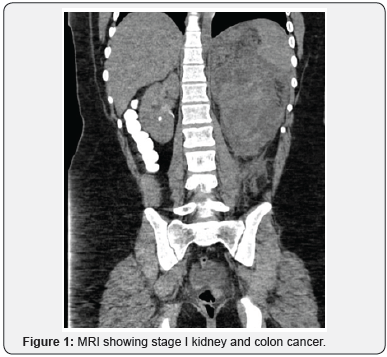

KP is a 14-year-old previously healthy adolescent with family history significant for Lynch Syndrome who presented to the emergency department with flank pain and urinary hesitancy. She was found to have a large mass in the abdomen on imaging, diagnosed as stage I kidney and colon cancer (Figure 1). She underwent left nephrectomy and hemicolectomy with ileostomy. Given family history of Lynch Syndrome, she had gene analysis confirming diagnosis of biallelic Lynch Syndrome.